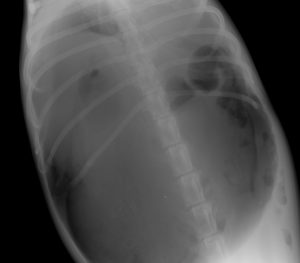

問診の時点で胃拡張・捻転症候群が強く疑われたため、診断のためのレントゲン検査を行った。

胃は非常に重度に拡張・捻転しており、呼吸も弱くなっていた。

緊急対応として胃を穿刺し、抜気した。

抜気後、やや胃が縮小した